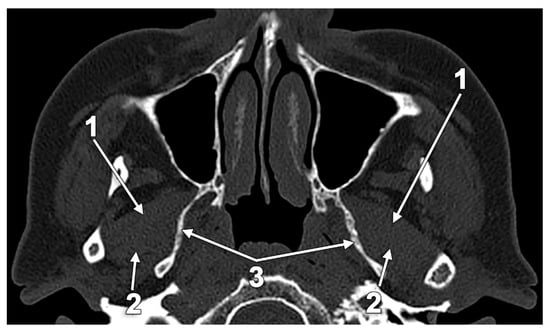

The Atrophy and Hypertrophy of the Lateral Pterygoid Muscle